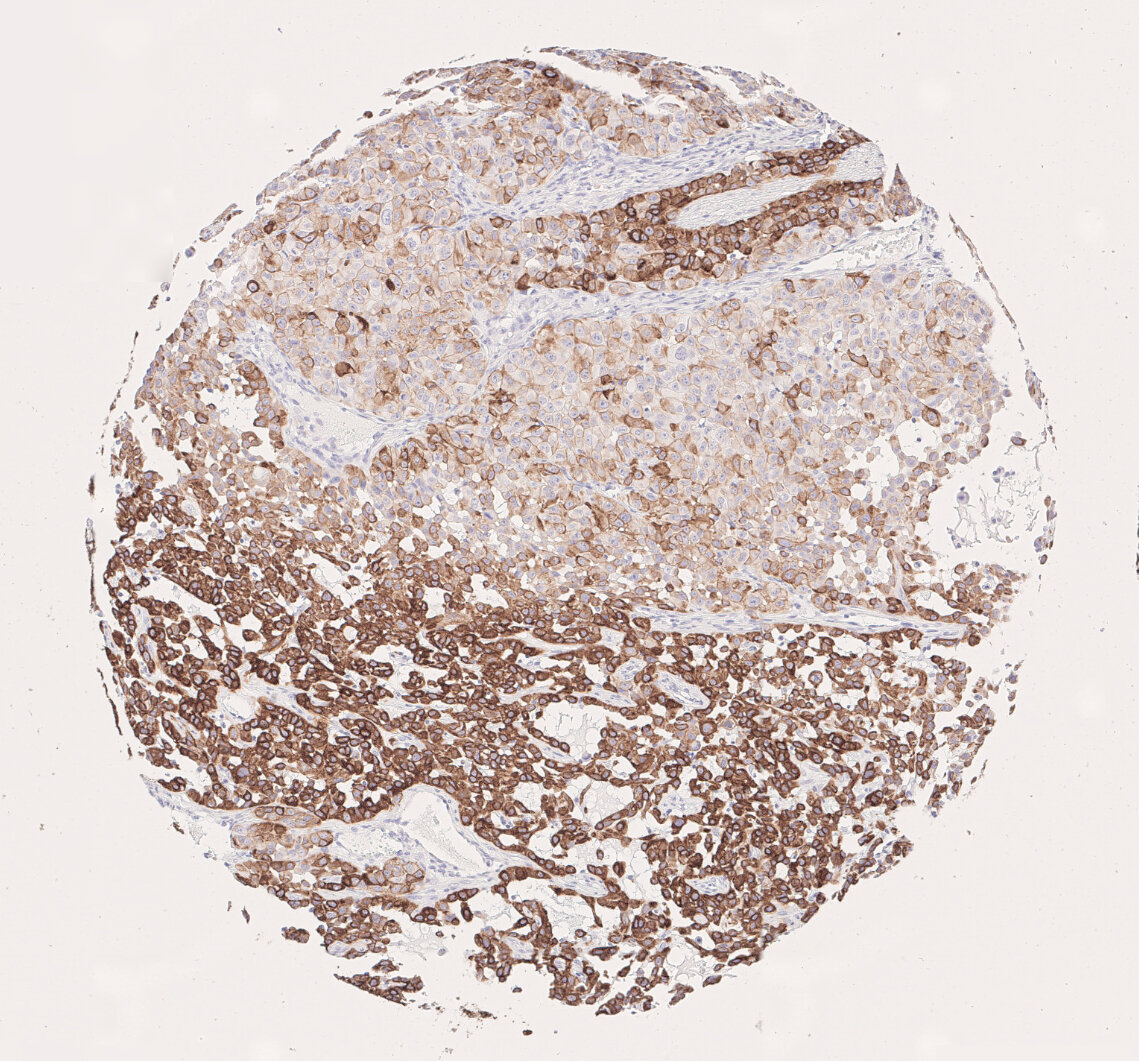

CK7 immunohistochemistry visualizes tumor heterogeneity in NSCLC adenocarcinoma subtype in a brownish color

Figure 6: CK7 immunohistochemistry visualizes tumor heterogeneity in NSCLC adenocarcinoma subtype.